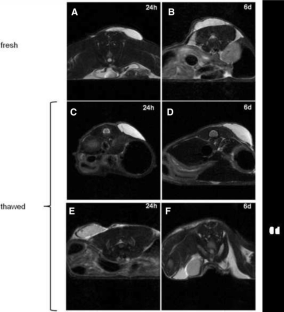

Cryopreservation of subcutaneous white adipose tissue (sWAT) avoids multiple surgeries in patients subjected to reconstructive procedure. Fat grafts were performed subcutaneously on 26 mice treated with fresh (13 mice) or cryopreserved (13 mice) human sWAT. Cytofluorometry for CD marker expression of stem cells, differentiation capability, and in vivo survival of fat grafts were evaluated. In vitro analysis evidenced that cryopreservation did not affect the stem potential of samples. In vivo MRI showed that grafts were well preserved in 13 mice treated with fresh sWAT, whereas in 13 animals treated with thawed fat, graft volumes were strongly reduced after 1 week. Ultrastructural studies performed both on fresh and thawed specimens demonstrated that grafts performed with thawed sWAT are able to store lipids more slowly with respect to grafts performed with fresh sWAT and adipocytes maintained a multilocular appearance. Collected data demonstrated that the protocol of cryopreservation could maintain the regenerative capability of the sWAT, but the rate of reabsorption after fat grafting is higher using cryopreserved sWAT. Maintaining the stem potential of sWAT after cryopreservation is a very important aspect for reconstructive and regenerative medicine. The employment of cryopreserved sWAT represents an interesting goal for surgeons. Surely there is the necessity to improve the protocol of cryopreservation.